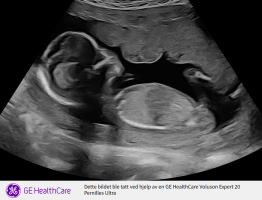

Dette må da være en gutt?Noen som vil tolke denne? 15+4. Vis vedlegget 459049

Gutt! Men det skal stadfestes på neste ul om 2 uker. Det kunne være navlestrengen de så, men de sjekket med temperatur (?) /farger og det så ut til at navlestrengen lå lenger opp.Og hva får du?![]()

Blir spennende å høre hva de sier om 2 uker da!Gutt! Men det skal stadfestes på neste ul om 2 uker. Det kunne være navlestrengen de så, men de sjekket med temperatur (?) /farger og det så ut til at navlestrengen lå lenger opp.